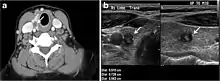

Fig. 8. A 48-year-old male patient post total thyroidectomy with PTC recurrence. a Transverse greyscale ultrasound of the neck demonstrates a left thyroid bed heterogeneous, predominantly hypoechoic irregular lesion with calcifications (white arrow). b A spot image of iodine 123 total body scan of the neck demonstrate a focus of abnormal radiotracer uptake at the left thyroid bed (Black arrows) between the annotated markers. c Enhanced axial CT scan of the neck demonstrates an enhancing large left thyroid bed mass (white arrow) with no calcifications. The lesion exerts a mass effect on the oesophagus (black arrow) and is inseparable from the trachea.[1]